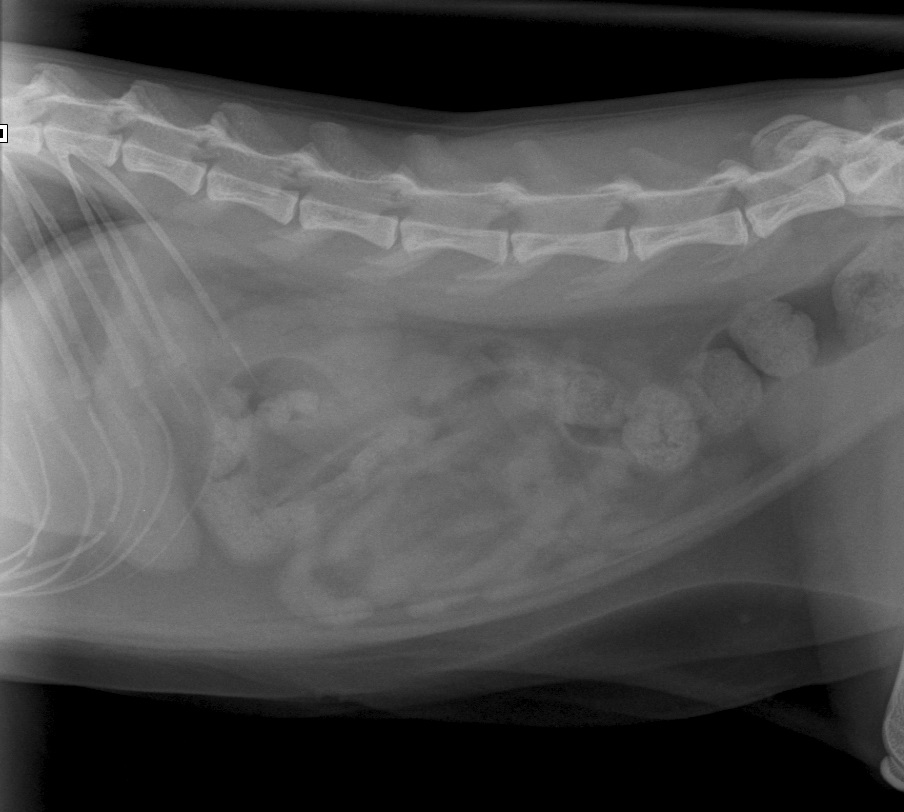

Op 11 augustus 2015 kwam de drie jaar oude poes Noortje op het spreekuur omdat ze zich niet lekker voelde. Ze had meerdere keren gebraakt en alleen een beetje water bleef binnen. Ze was verder iets rustiger dan normaal, maar zeker niet doodziek. We hebben haar goed onderzocht en afgezien van een iets gevoelige buik vertoonde Noortje geen afwijkingen. Voor de zekerheid hebben we een röntgenfoto van haar buik gemaakt en daar waren geen grove afwijkingen op te zien.

Noortje5De buik van Noortje op de röntgenfoto